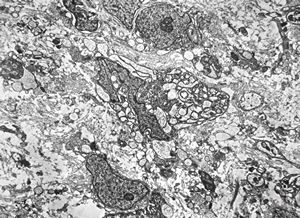

F,69y. | cystadenoma (Warthin tumor) … caruncula - (modified mitochondria in an autolysed sample)